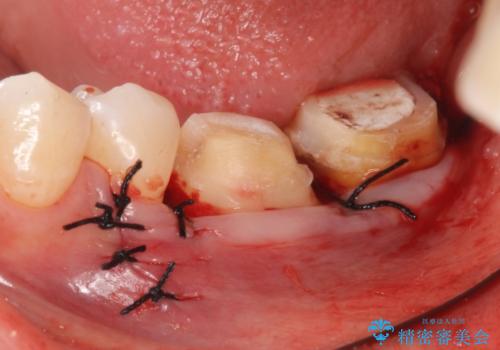

また左下6は遠心にあった歯茎より深い虫歯(縁下カリエス)の問題を解決するため、歯茎を下げる歯周外科手術を行いました。

歯周外科手術終了後、歯茎の回復を待ち左下6、7ともにオールセラミッククラウン(スタンダード)による補綴を行いました。

- オールセラミッククラウン…¥100,000×2、仮歯…¥10,000×2、歯冠長延長術…¥100,000費用は治療当時の料金となります